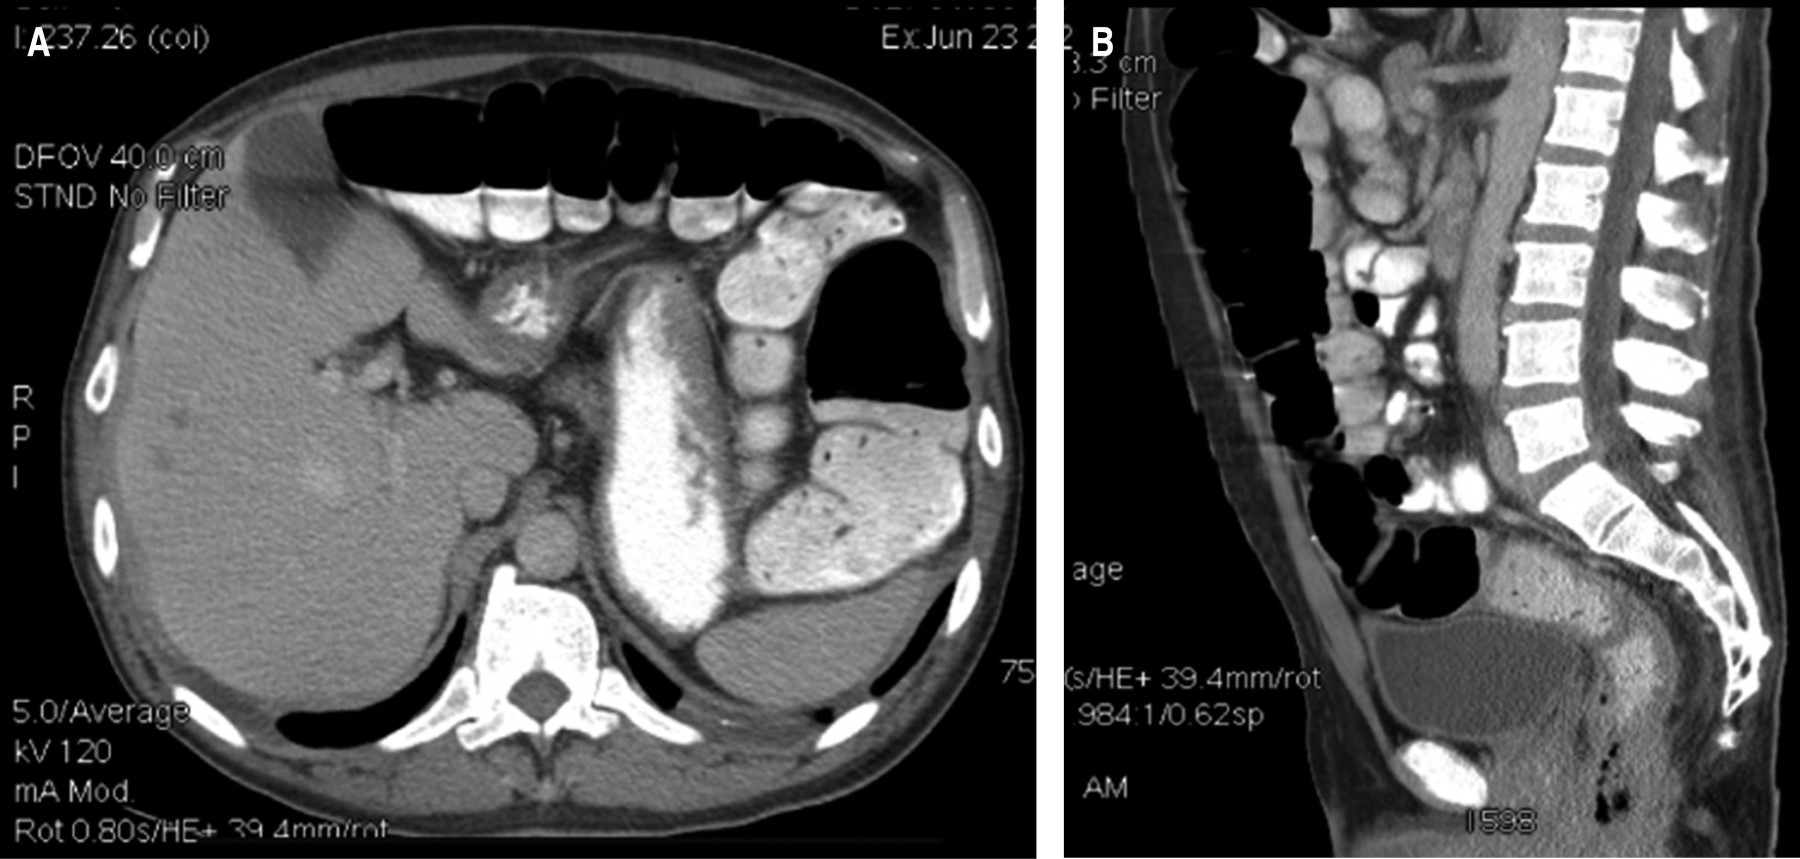

La tomografía mostró un absceso retroperitoneal en el lado izquierdo que diseca hasta la región glútea y muslo ipsilateral, así como un engrosamiento de la pared del recto, también se evidenció la presencia de lesiones hipodensas en el parénquima hepático compatibles con metástasis tumorales (Figuras 1 y 2).

La tomografía axial computarizada (TAC) es el estudio de elección en el diagnóstico y etapificación de esta complicación infecciosa-neoplásica, con una sensibilidad del 95%, aunque a veces no es posible identificarla hasta la intervención quirúrgica.13 La TAC puede mostrar neumatosis colónica hasta en el 16% de los pacientes, y puede ser un signo de inminente perforación.5 Se pueden observar colecciones con densidad de líquido, aire libre retroperitoneal, cambios en la grasa pericólica y engrosamiento de la pared colónica, sin embargo, estos cambios también pueden producir enfermedades benignas, por lo que el diagnóstico prequirúrgico es difícil.5

Figura 1